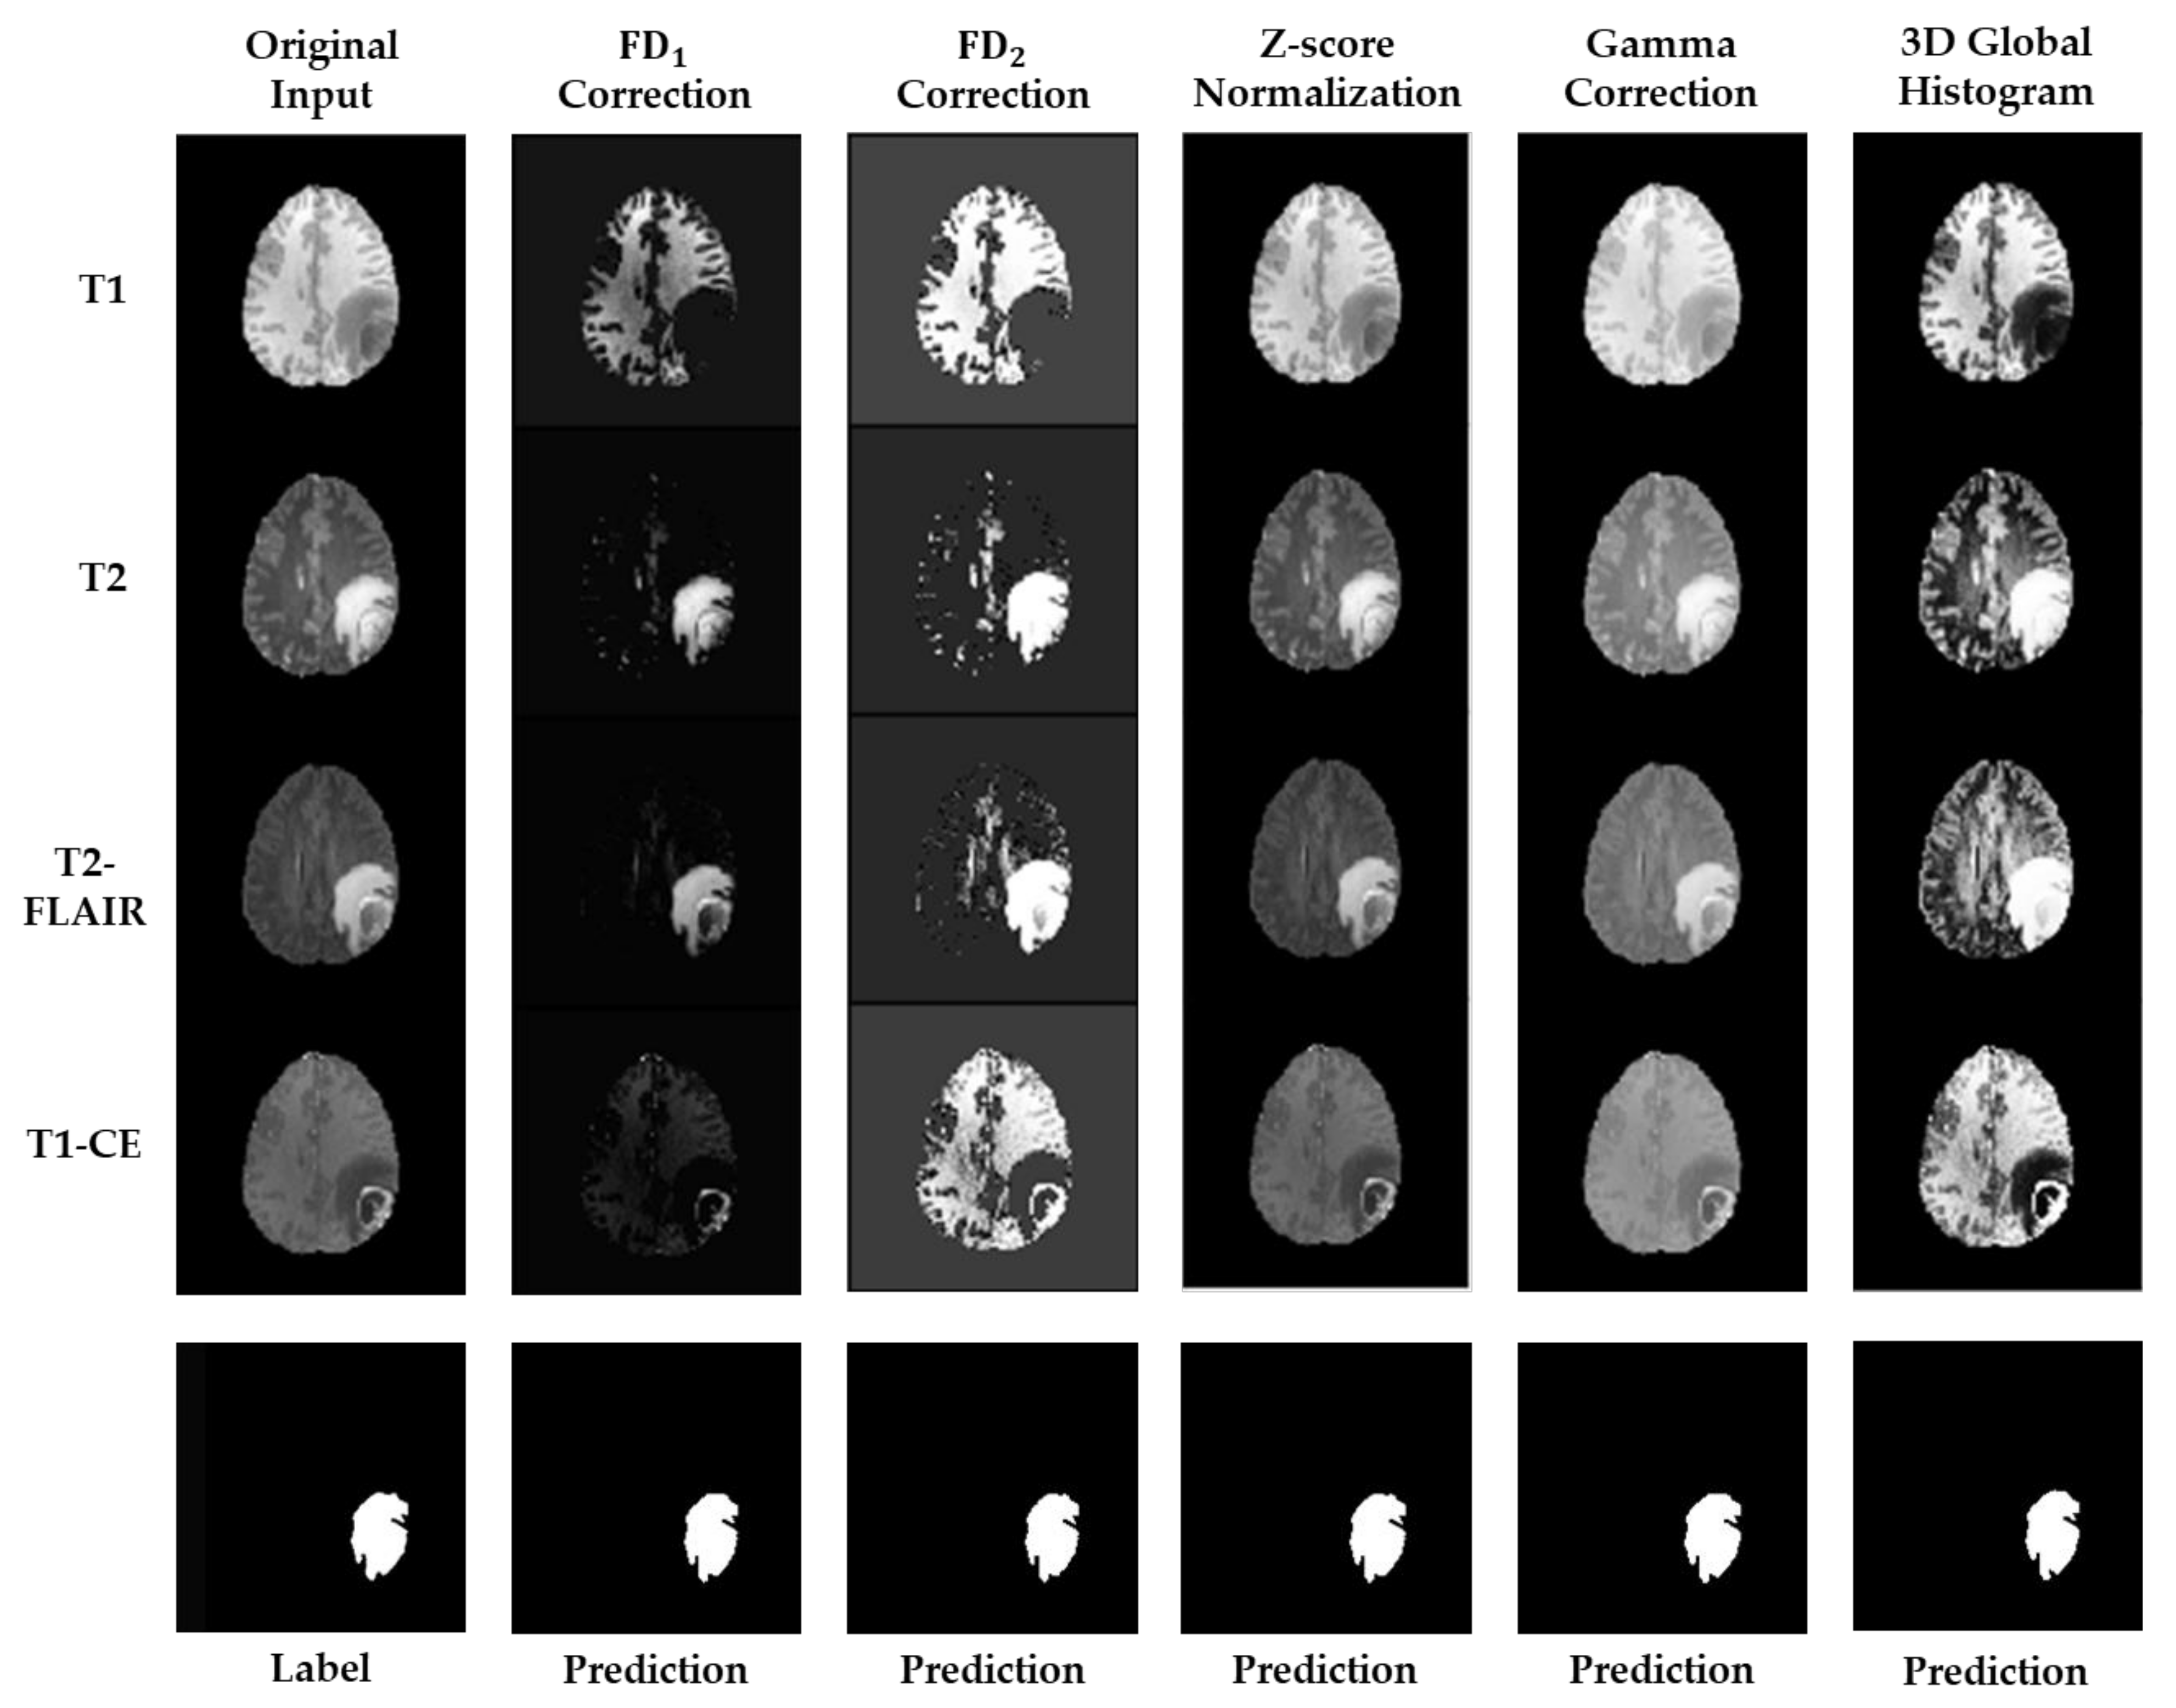

| Preprocessing Method | Dice Score (WT only) | Computational Time (min) |

|---|---|---|

| Null | 0.7183 | 91 |

| z-score Normalization | 0.9296 | 142 |

| 3D Global Histogram Equalization | 0.9148 | 84 |

| Gamma Correction 1 | 0.9319 | 93 |

| correction | 0.9431 | 88 |

| correction | 0.9347 | 90 |